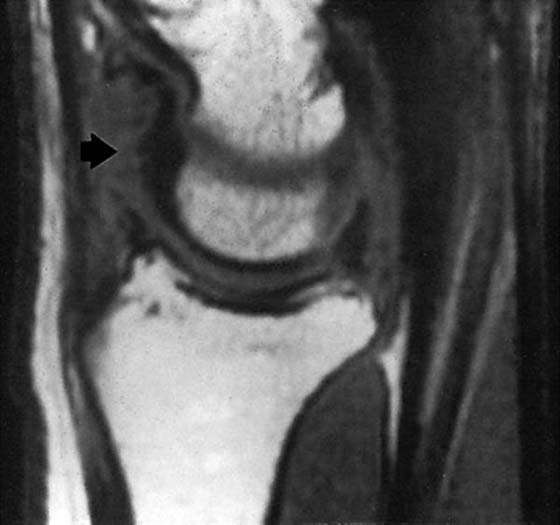

MRI is of great value in defining soft tissue abnormalities (Figs. 13-17 to 13-19, all online). In the evaluation of tumors, it cannot provide a specific diagnosis, but it can define the size of the lesion and the extent of involvement of marrow and neurovascular structures (Fig. 13-20, online).27 Other soft tissue abnormalities diagnosed more easily by MRI include ganglions, ligament tears, and cartilage abnormalities (Fig. 13-21).28,29 Dorsal wrist pain can be attributed to hypertrophy of the dorsal capsule as well as ganglions that may be occult and not palpable. Patients with dorsal wrist pain of unknown origin are therefore candidates for MRI evaluation. MRI is especially helpful in diagnosing tears of the scapholunate and lunotriquetral ligaments, particularly when dissociation of the scapholunate is not evident on plain films.30 Excellent depiction of the TFC can be achieved with MRI, but the image must be interpreted carefully; thinning of the disk occurs in many patients, but a tear of this structure is not diagnosed unless an avulsion from the ulnar or radial insertion can be observed.31-33

Evaluation of the bony structures begins with routine plain views. If the bone density is increased, advanced Kienböck’s disease is a possibility; otherwise, early AVN of the lunate must be ruled out. Bone scintigraphy is then performed and, in Kienböck’s disease, may show decreased uptake within the first 48 hours and then increased uptake as the bone repairs. Bone scintigraphy is nonspecific, however, and demonstrates increased uptake wherever bone turnover is increased, such as in joints with synovitis. It also provides poor anatomic resolution and does not effectively distinguish between the joint space and the bone. MRI provides far greater resolution than bone scintigraphy in the evaluation of AVN. It also can reveal pathology of the bone vascularity earlier than any other imaging techniques (Fig. 13-29).

Figure 13-29 Avascular necrosis of the lunate (arrow). Coronal magnetic resonance image shows a dark area in the marrow. The corresponding nuclear medicine scan is seen in Figure 13-14.